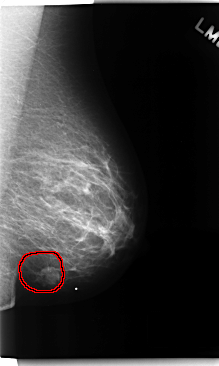

C_0161_1.LEFT_CC

LEFT_CC LINES 4712 PIXELS_PER_LINE 2696 BITS_PER_PIXEL 12 RESOLUTION 50 OVERLAY

FILE: C_0161_1.LEFT_CC.OVERLAY

TOTAL_ABNORMALITIES 1

ABNORMALITY 1

LESION_TYPE MASS SHAPE LOBULATED MARGINS MICROLOBULATED

ASSESSMENT 5

SUBTLETY 5

PATHOLOGY MALIGNANT

TOTAL_OUTLINES 1

BOUNDARY